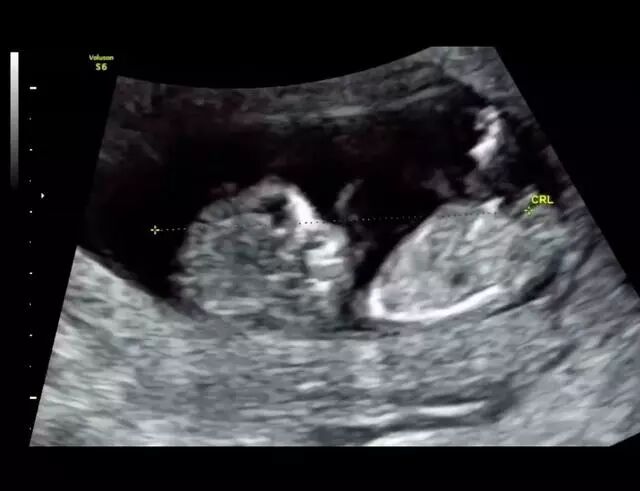

2月1日,潘玮柏更新微博晒出了和好友李晨儿子的合照,本身就是大孩子性格的潘玮柏碰上小伙伴,秒变潘三岁,画风可以说是非常可...